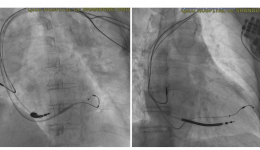

• 山东大学齐鲁医院(青岛)心内科结构性心脏病团队应用DragonFly™完成高危复杂二尖瓣极重度反流TEER手术

山东大学齐鲁医院(青岛)心内科结构性心脏病团队应用DragonFly™完成高危...

山东大学齐鲁医院(青岛)结构性心脏病团队在心内科学科带头人钟敬泉教授、科室主任姚桂华教授、副主任由倍安教授的支持指导下,在麻醉科副主任周金峰、心外科副主任霍玉峰等支持下,心内科结构心脏病医疗组长孟庆峰副主任医师带领结构心脏病团队为...